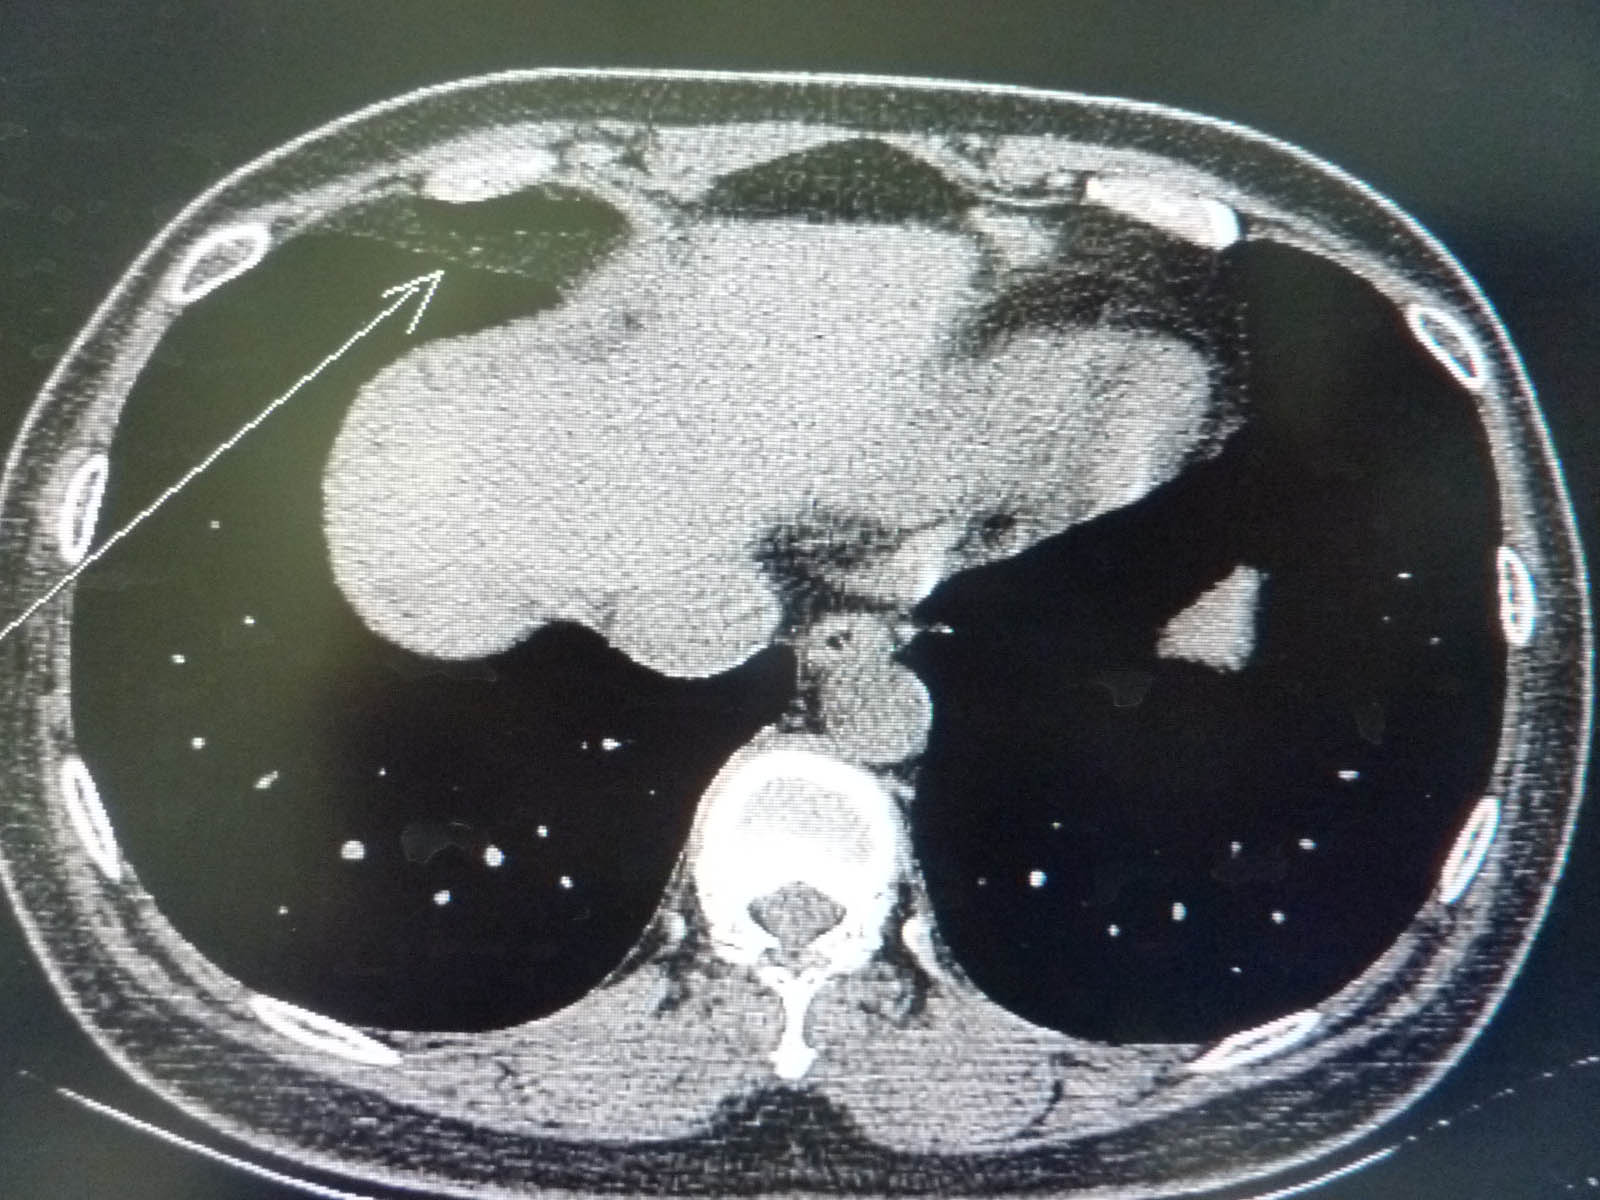

CT49612:乳腺癌术后一年复查

右肺内箭头指示是斜裂增厚?

肺下韧带

在斜裂走行区域,纵隔窗与脂肪同密度,可能就是局部胸膜脂肪增厚了,无什么临床意义。

叶间胸膜增厚。